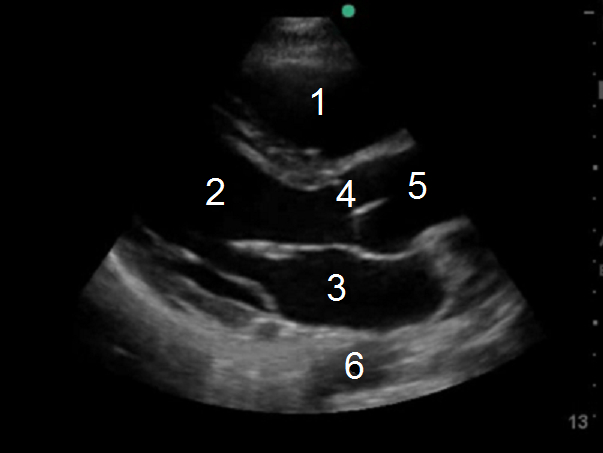

1. Right Ventricle (RV)

2. Left Ventricle (LV)

3. Left Atrium (LA)

4. Aortic Valve (AV)

5. Ascending Aorta

6. Descending Aorta